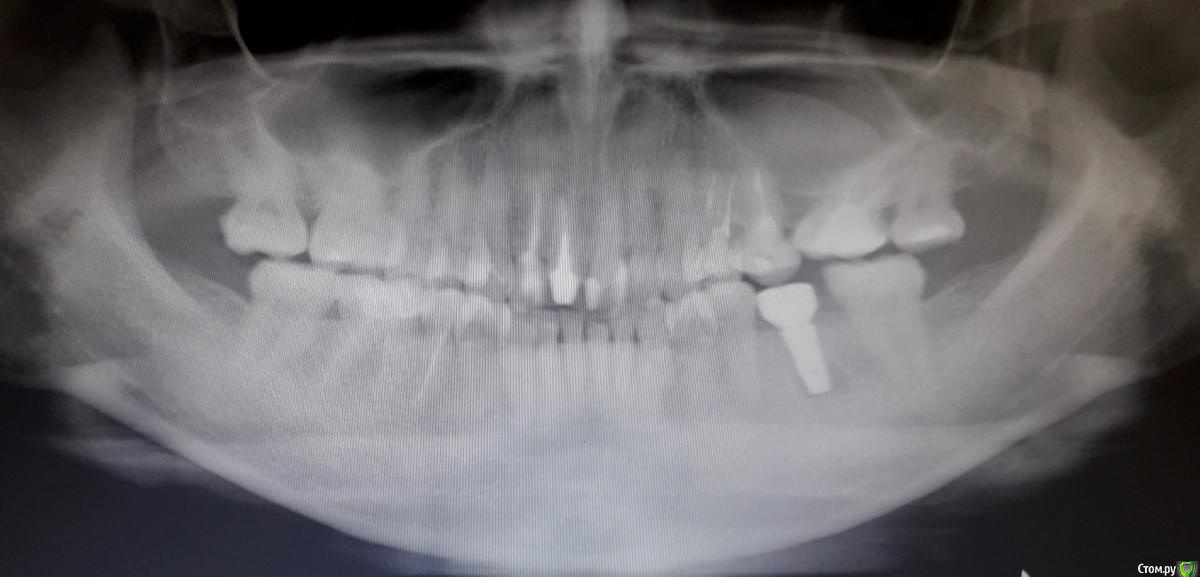

Nata26 Опубликовано 22 июля, 2020 Автор Поделиться Опубликовано 22 июля, 2020 Прикладываю панорамный снимок. Беспокоит зуб на нижней челюсти слева, 37. Есть КТ-снимок, записанный на диск, но у меня компьютер без дисковода, поэтому без КТ. Ссылка на комментарий

колесников Опубликовано 22 июля, 2020 Поделиться Опубликовано 22 июля, 2020 В вашем случае не нужно ждать,надо удалить и сразу поставить имплант,прекрасные условия для этого. Хотел бы обратить внимание на верхний зуб над причинным ,на верхнюю шестерку слева. Покажите снимок ортопеду,этот зуб необходимо покрыть коронкой ,чтобы он выдержал нагрузку в контакте с нижним имплантом,но есть вопросы. 2 Ссылка на комментарий